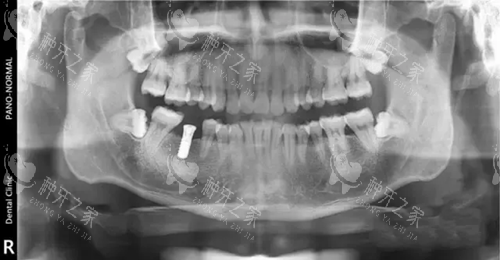

影像学评估:通过CBCT测量骨高度、宽度及密度。